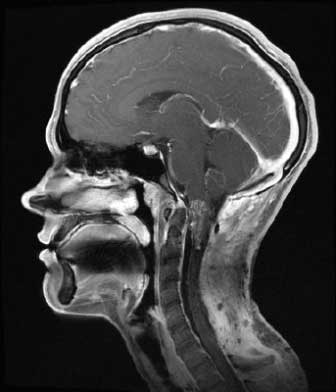

- МРТ – этот метод обладает высокой точностью, достигающей 99%. МРТ позволяет оценить изменения в паутинной оболочке, определить местоположение кисты и исключить другие заболевания с похожими симптомами, такие как опухоли и абсцессы.

Как МРТ покажет арахноидит головного мозга?

Слипчивый арахноидит характеризуется слипанием нервных корешков и спинного мозга, которые могут выглядеть как слипшиеся пучки на МРТ-снимках. Этот признак лучше всего виден на Т2-взвешенных изображениях. Повышенный сигнал от окружающих тканей на Т2-взвешенных изображениях указывает на отек и воспаление.